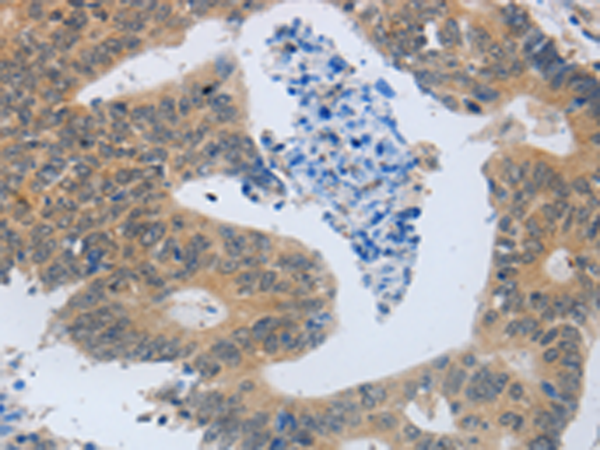

分类: 科研抗体货号: P11043别名: TBM; leB; MUC5; mucin应用: IHC反应种属: Human